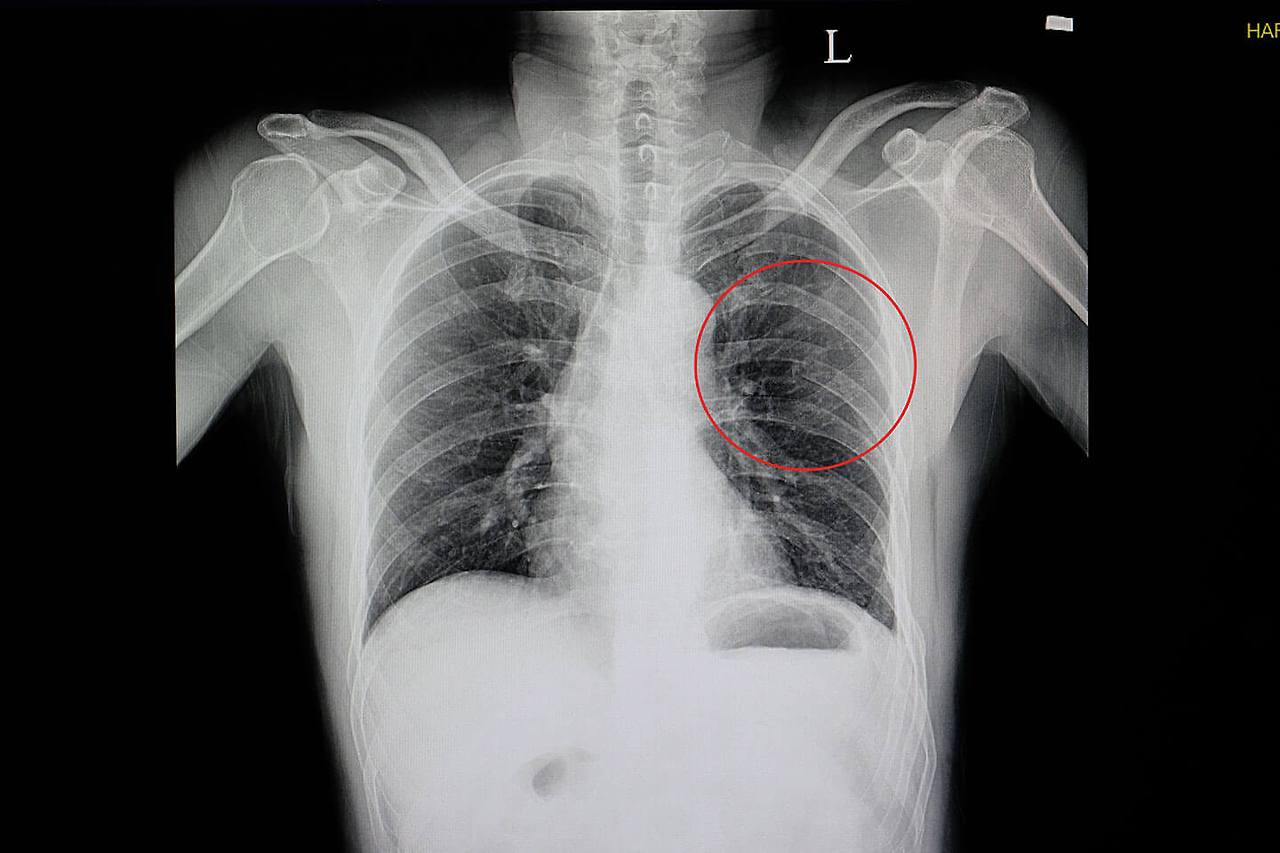

갈비뼈 금이 갔을 때의 증상

갈비뼈가 금이 갔을 때에는 다음과 같은 증상이 나타날 수 있습니다:

- 통증: 금이 간 부위 주변에서 강한 통증이 느껴집니다.

- 불편한 움직임: 갈비뼈가 금이 갔을 때는 그 부위를 움직이는 것이 어려울 수 있습니다.

- 부종: 금이 간 부위 주변에 부종이 생길 수 있습니다.

- 반응성: 갈비뼈가 금이 간 부위에 압력이 가해지면 통증이 증가할 수 있습니다.

이러한 증상이 나타난다면 즉시 의료진의 도움을 받는 것이 중요합니다.